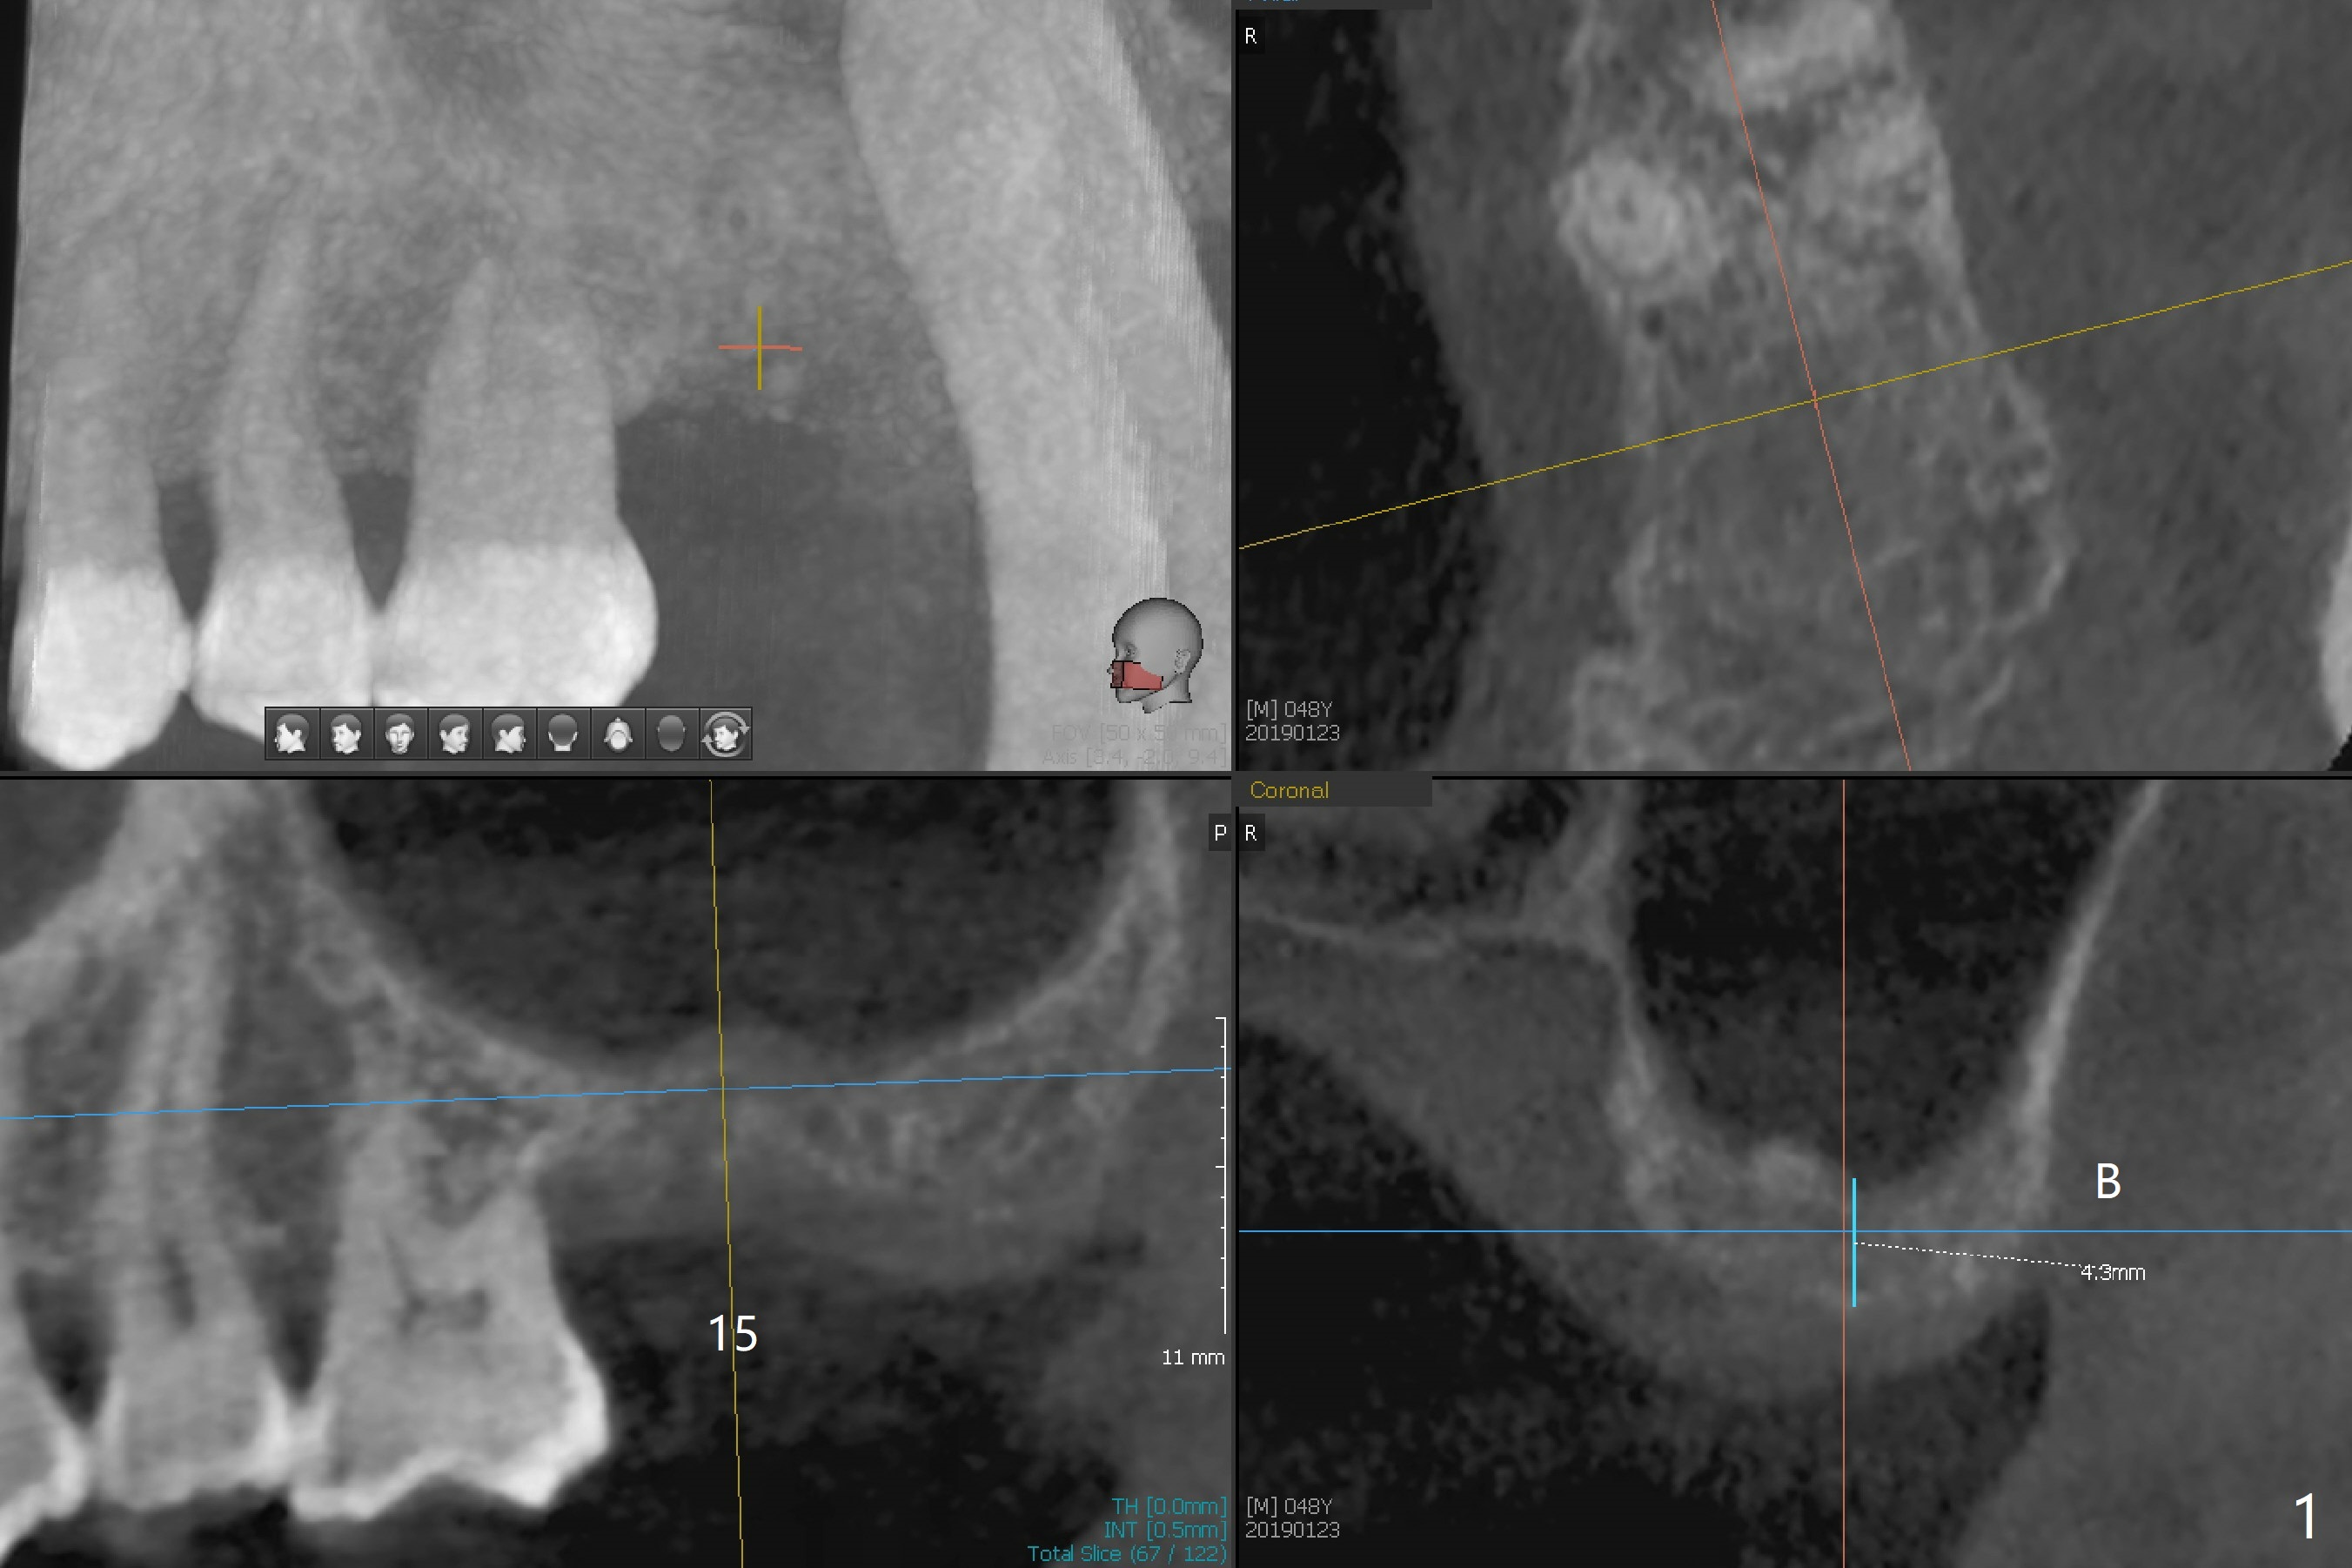

A 48-year-old man returns for CT 4.5 months post infected implant removal with bone graft at #15. The bone height reduces from 6-10 mm to ~ 4 mm (Fig.1). To place a 5x7.3 mm implant (Fig.2), initial osteotomy for ~3 mm in depth and in diameter will be aided by guided surgery (Fig.3 (red line: sinus membrane)). Internal sinus lift is going to be conducted with Magic Lifter free hand or in the middle of the tube (Fig.4 arrows). The specially designed lifter is able to lift the sinus floor without tearing the membrane. To prevent and repair membrane injury, one or 2 pieces of PRF membrane will be inserted underneath the lifted structures (Fig.5 yellow), followed by bone graft (green circles). Then 3.5-4.5 mm taps will be used with guide to further expand and condense the osteotomy. With more graft to be placed, the 5x7.3 mm implant will be placed (Fig.6 pink).